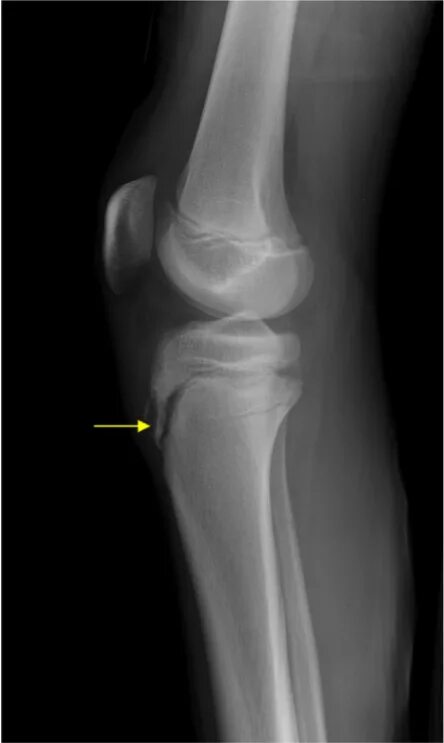

Болезнь осгут шляттера